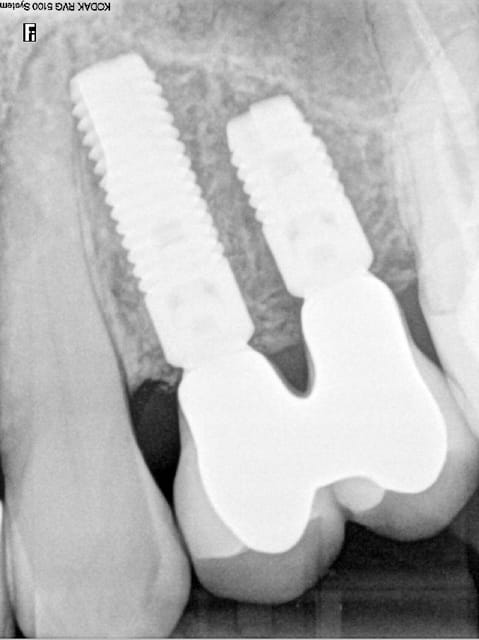

contrôle à 2 ans, niveau osseux pas trop mal.

Controle2ans a3nyrb - Eugenol